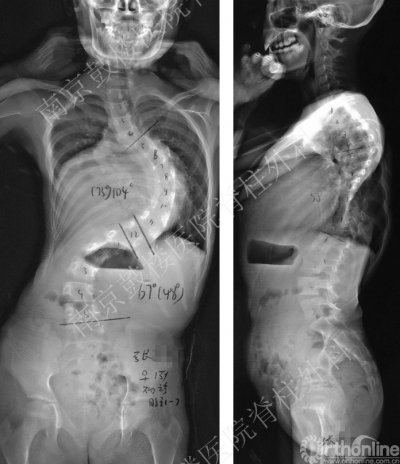

南京鼓楼医院脊柱外科近日接诊了一位特殊的15岁侧弯女孩,站立位全脊柱片显示其胸椎侧弯已达104°,此外还合并房间隔缺损及重度肺动脉高压且已经出现右向左分流,患儿入院时面部、口唇、躯干及肢体均呈现紫色。入院时血气分析结果提示氧分压45mmHg,氧饱和度仅为83%,心肌酶谱中BNP高达1720pg/ml,cTNT0.149ug/L,肺动脉压已至108mmHg,肺功能检测显示为重度限制性通气功能减退,诸多数据均提示其心肺功能已至终末期。为此,患儿父母近年来已咨询国内多家三甲医院,除每日口服药物降低肺动脉压以外,医生告知其只有进行心肺联合移植才可能让其延续生命,但前提是必须先进行脊柱矫正手术改善胸廓容积,否则无法放置移植心肺。

患儿就诊时全脊柱正侧位片